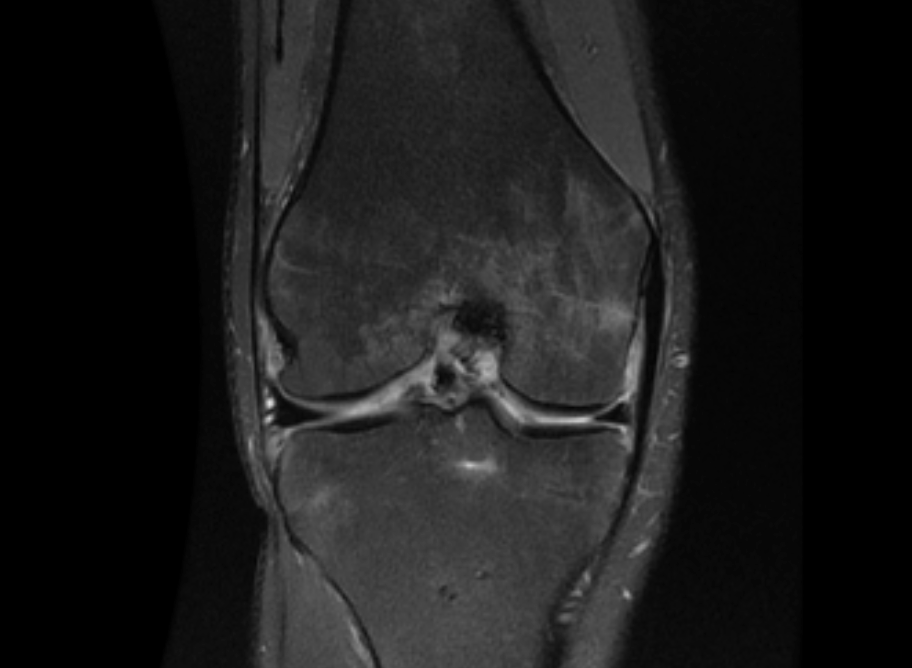

Post-Operative MRI Showing Anatomic Healed Avulsion Fracture in Coronal View